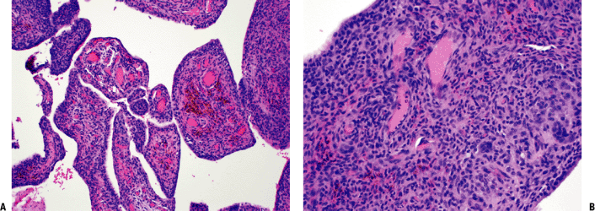

![]() |

Figure 11-10 (A) Plantar fibromatosis: dense fibrous proliferation infiltrating adipose tissue. (B)

Plantar fibromatosis: early lesions consist of cellular proliferations of bland-looking spindle cells and collagen deposition similar to desmoid tumors. Older lesions tend to be less cellular and contain more collagen. |